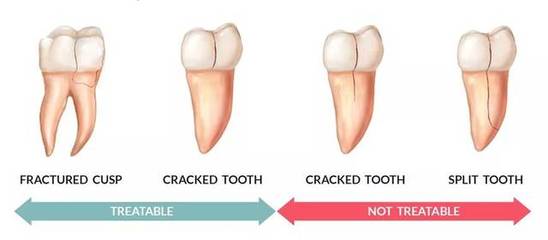

问医生。明明没有蛀牙,为什么牙齿又酸又痛?有的患者说没有蛀牙,但是冷喝会酸,烫吃会疼。也许他们咬了什么东西,突然疼得很厉害,甚至在睡觉的时候。为什么?其实这很可能是“裂牙”的一个毛病。裂,又称“不完全裂”或“微裂”,是指牙冠表面细小的非物理性裂纹,通常不易察觉。裂牙不像完全断牙。更像是防弹玻璃。想破也破不了。

我们的牙齿不是很硬,怎么说裂纹呢?牙齿结构也有其薄弱环节。比如正常牙齿结构中的发育沟、凹坑沟、釉盘等,都是牙齿发育留下的缺损区域,不仅抗裂性低,而且是牙齿承受正常咬合力时应力集中的地方,容易出现隐裂。除了牙齿结构缺陷的原因外,还与牙齿的使用方法不对有关。比如长时间用力过猛,如果平时喜欢用力咀嚼,牙齿会长得比正常大;或者定时啃骨头和坚果,用牙齿当“开瓶器”,或者吃特别硬的东西;或者同时吃太冷太热的东西都有可能导致牙齿开裂。

但去医院检查,医生告诉他,牙齿没有蛀牙,牙龈也没有萎缩。牙齿没有洞,为什么会疼?原来,经过仔细检查,患者的牙齿有裂痕。从肉眼来看,牙齿的裂缝没什么,只是一条细细的裂缝,应该不会引起牙疼。然而,在显微镜下,牙齿的裂缝看起来像一个开放的裂缝。外界冷热刺激随时进入牙齿的神经腔,引起疼痛。同样,当裂纹进一步加重时,细菌产生的毒素会侵入牙神经,导致牙神经发炎。